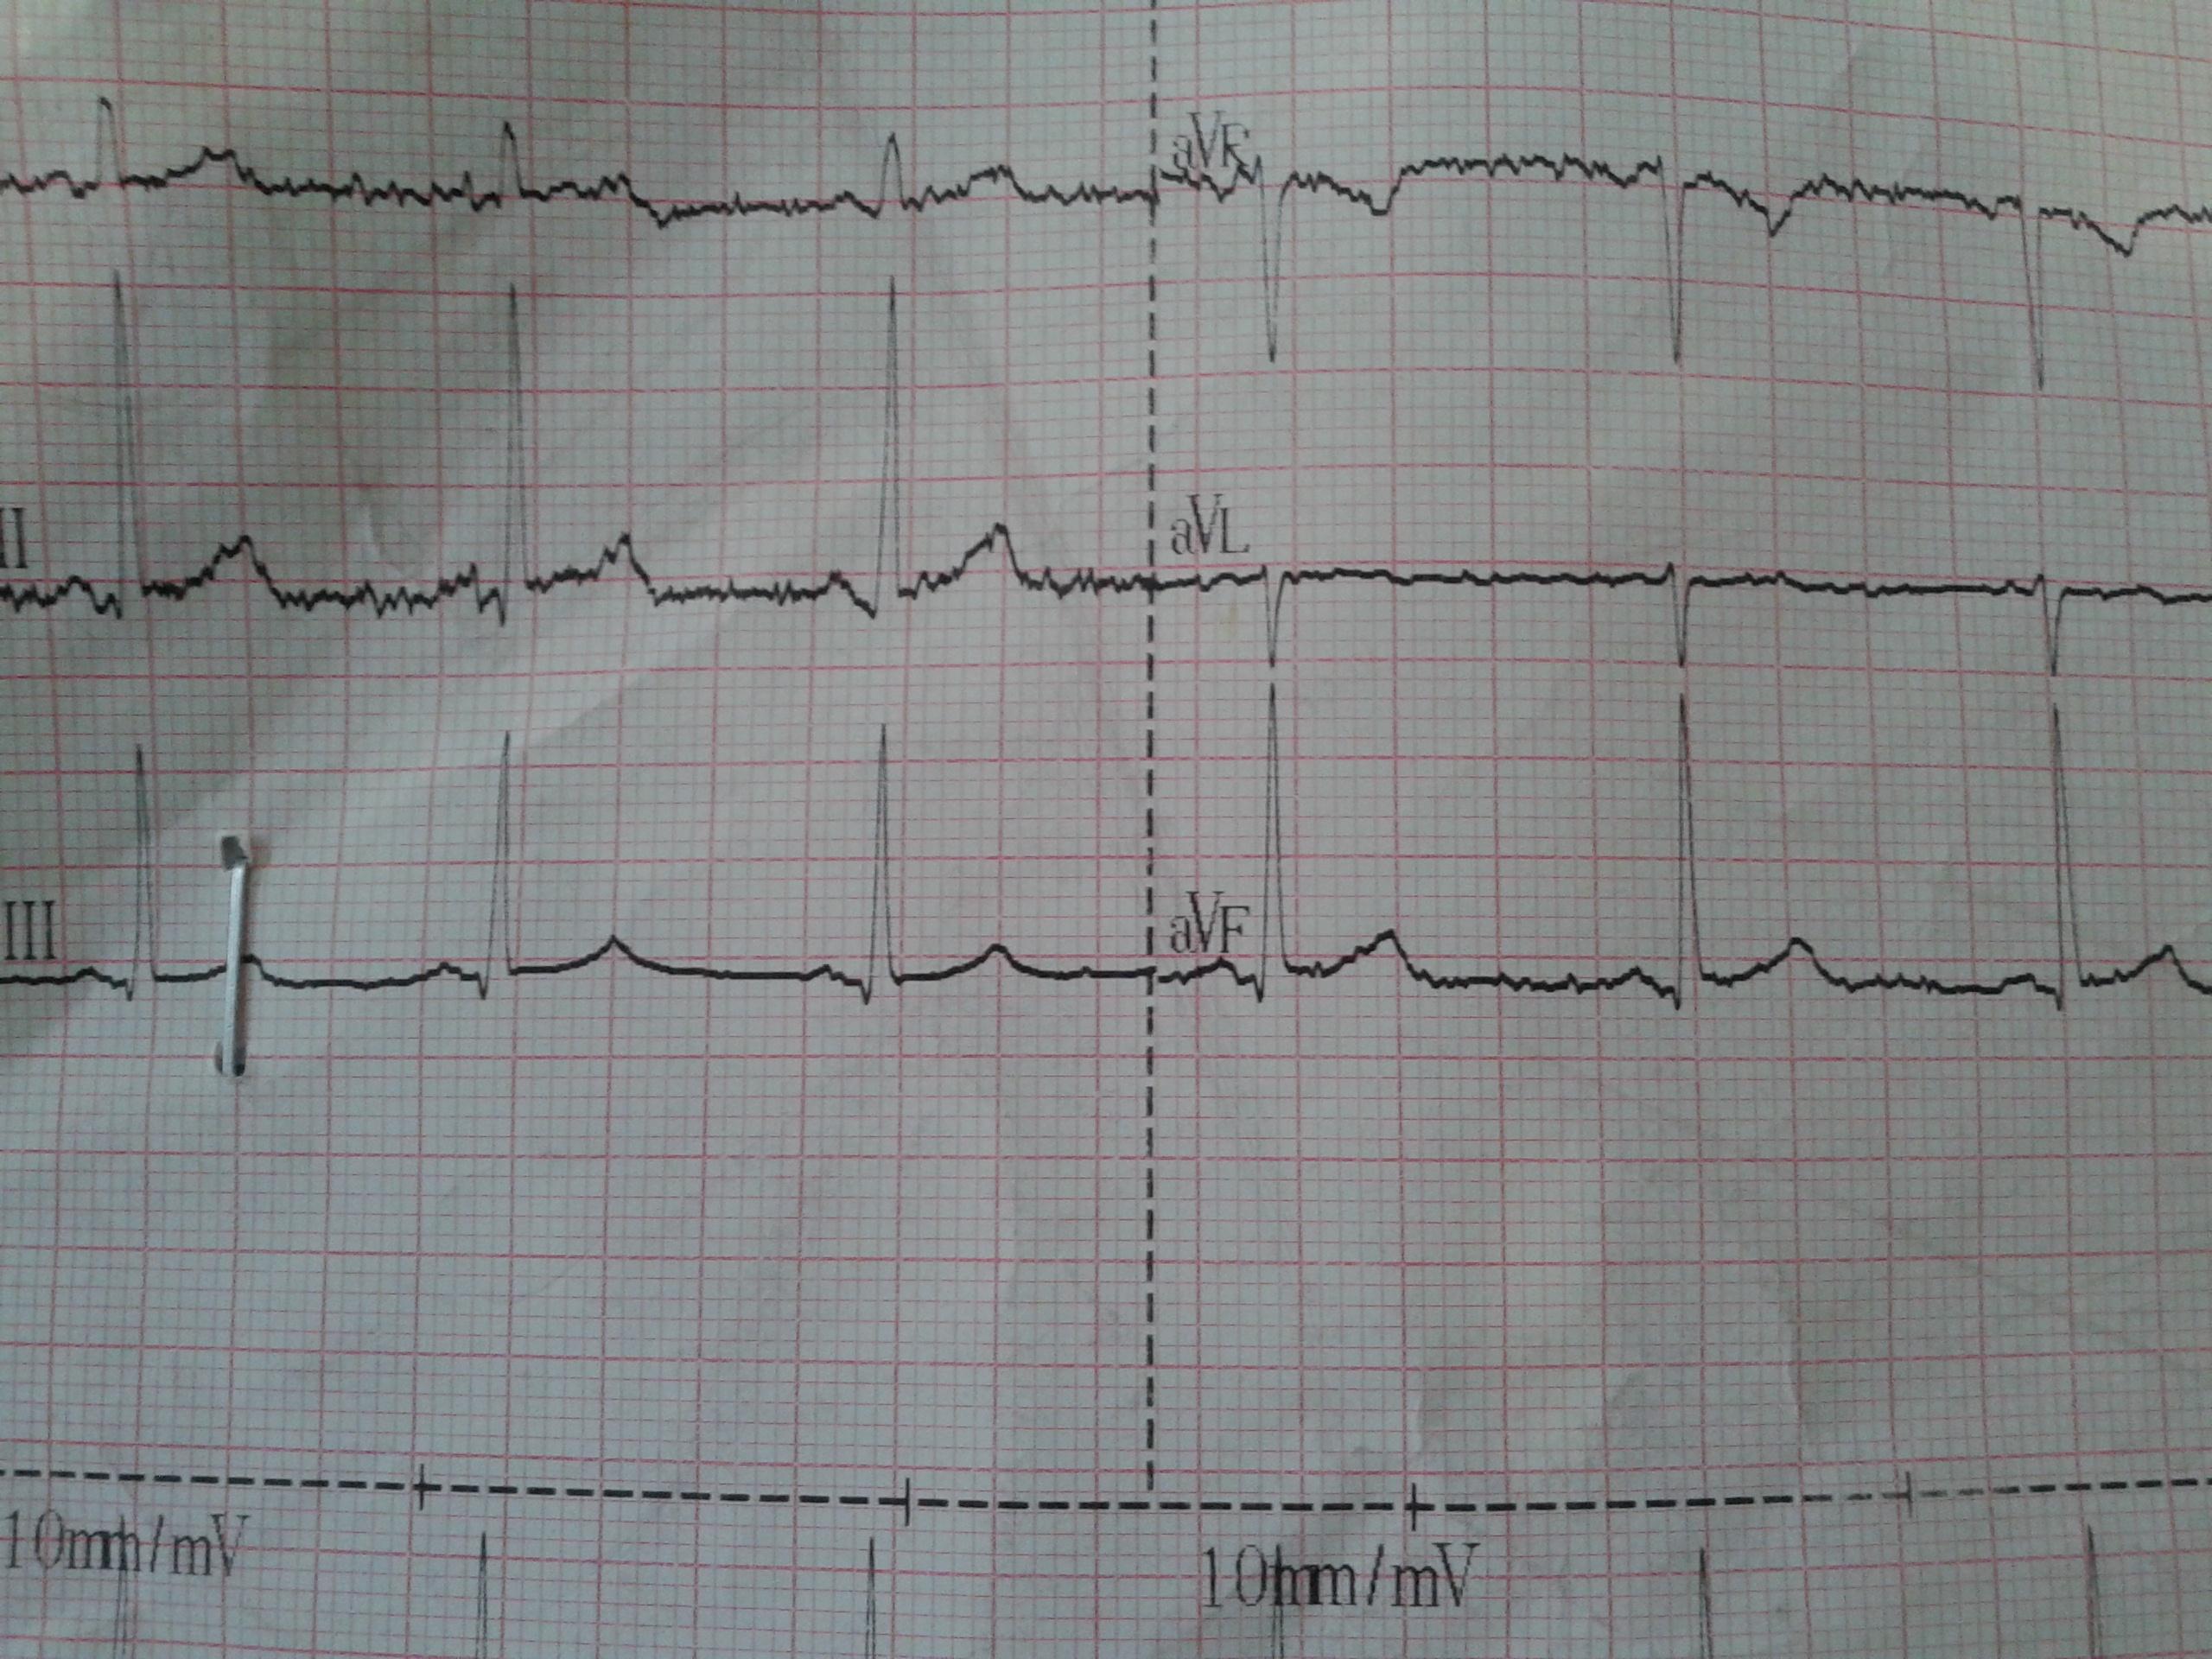

典型心电图分享:室性早搏二联律,长期高血压病史,感冒后引起判定为室性早搏。本心电图上出现:正常+室早-正常+室早-正常+室早样的组合,且连续重复三次以上,由此判定其为室性早搏二联律。RV5 2.5mV,由此判定其为左心室高电压。 3、ST-T分析 该患者ST段在Ⅰ、Ⅱ、aVF、V4-V6导联下移幅度大于0.05mV,由此判定其为ST段异常。 4、临床...